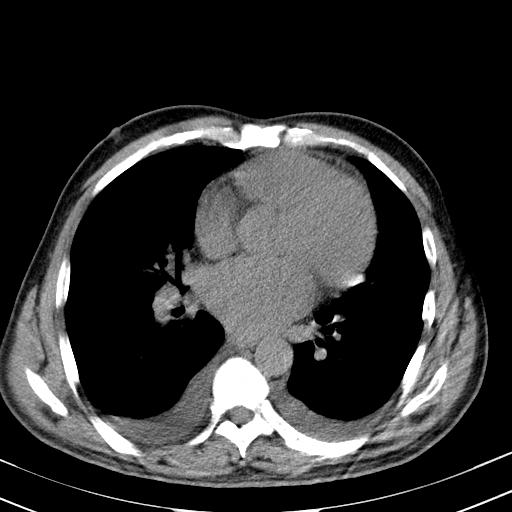

以下是引用zjzjr在2010-3-21 17:39:00的发言:[br]右下中心型肺癌并阻塞性肺炎/不张,纵膈淋巴结肿大,右侧大量胸腔积液,左侧少量胸腔积液

以下是引用zxl51642在2010-3-21 17:06:00的发言:[br]右下中心型肺癌并阻塞性肺炎/不张,纵膈淋巴结肿大,右侧大量胸腔积液,左侧少量胸腔积液,少量腹水。建议纤维支气管镜进一步检查。